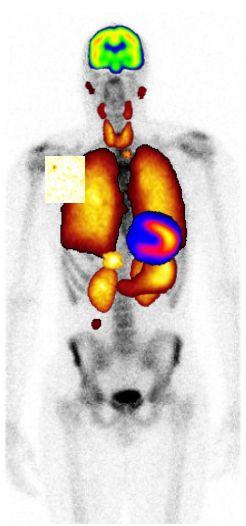

Nukleærmedisin/PET-senter er del av Radiologisk avdeling på Haukeland Universitetssykehus.Vi utfører alle nukleærmedisinske undersøkelser og terapier i Vestland. PET-senteret har 1 PET/CT, 1 PET/MR og egen radiokjemi/radiofarmasi med syklotron til lokal produksjon av radioaktive legemidler, bl.a. [18F]FDG, [11C]metionin, [18F]FLT, [18F]FMISO, [18F]FDOPA, [13N]amoniakk (de siste 5 som eneste i Norge), [68Ga]DOTATOC og [18F]PSMA-1007. Vi utfører radionuklidbehandlinger ([131I]jod for godartete og ondartete thyreoideasykdommer, [131I]MIBG for tumores av det sympatiske nervesystemet og [177Lu]DOTATATE for nevroendokrine tumores).